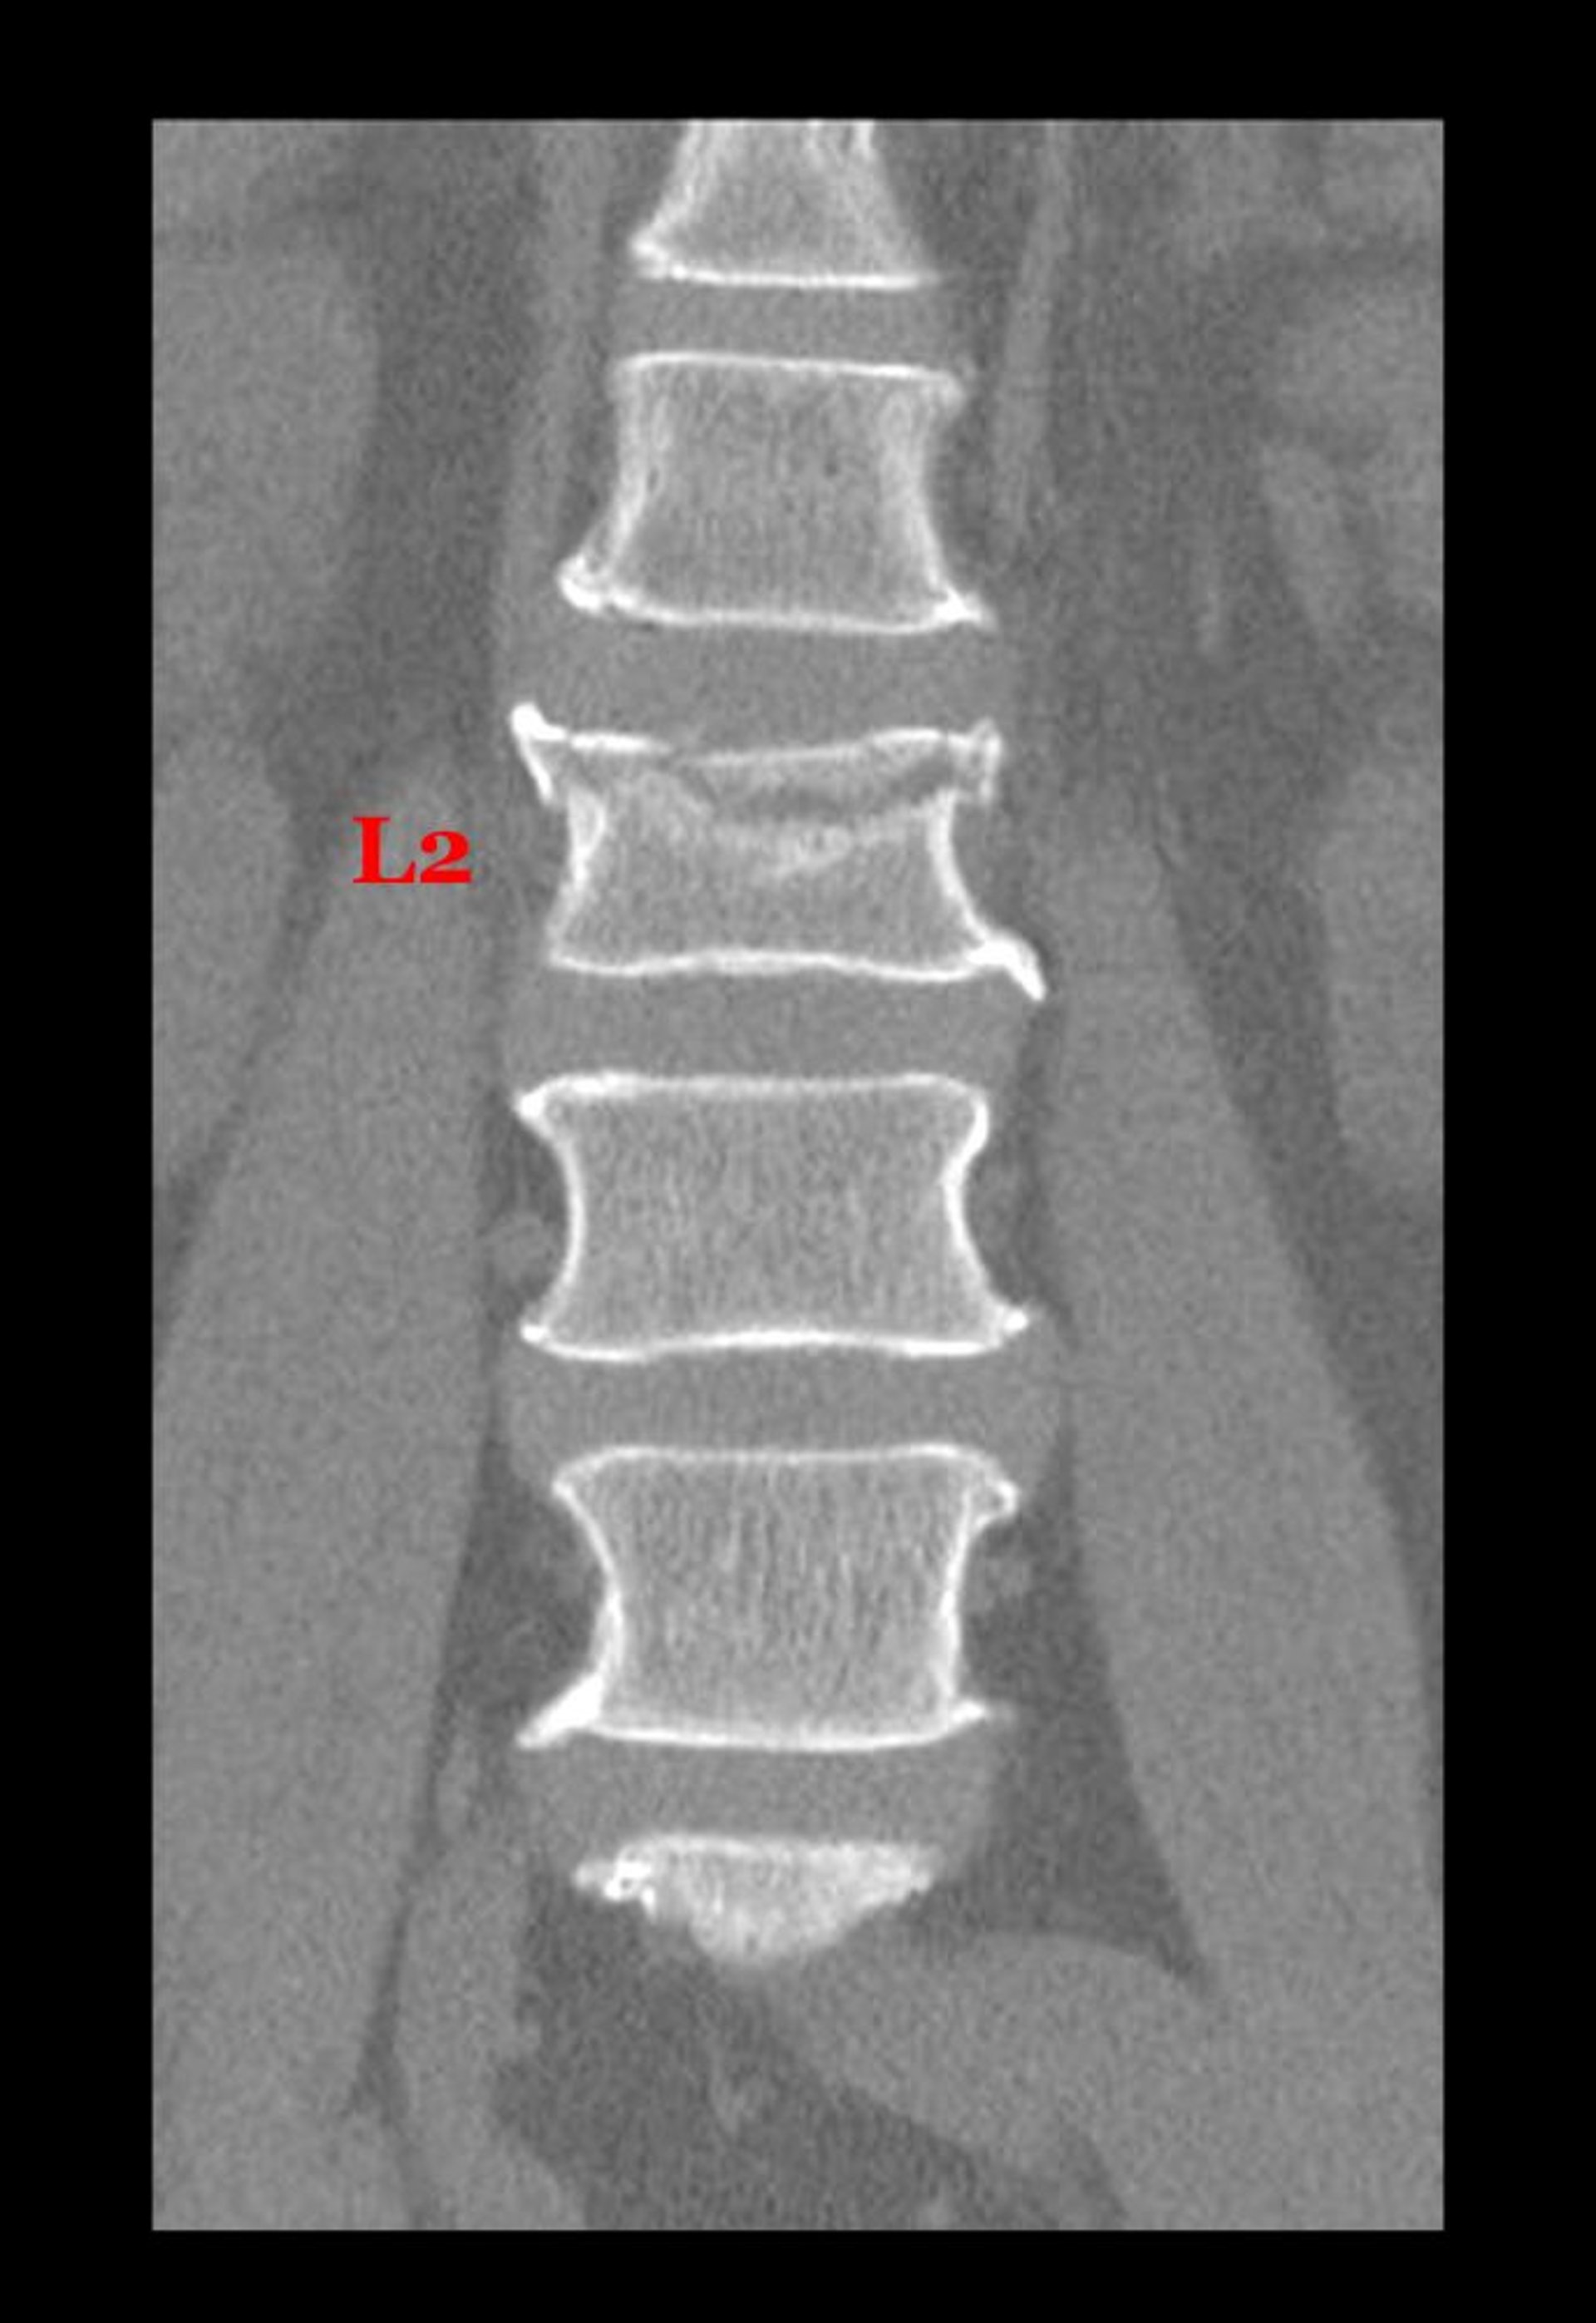

Компрессионный перелом поясничного позвонка

Этот корональный (фронтальный) срез КТ показывает перелом тела 2-го поясничного позвонка по верхней поверхности.